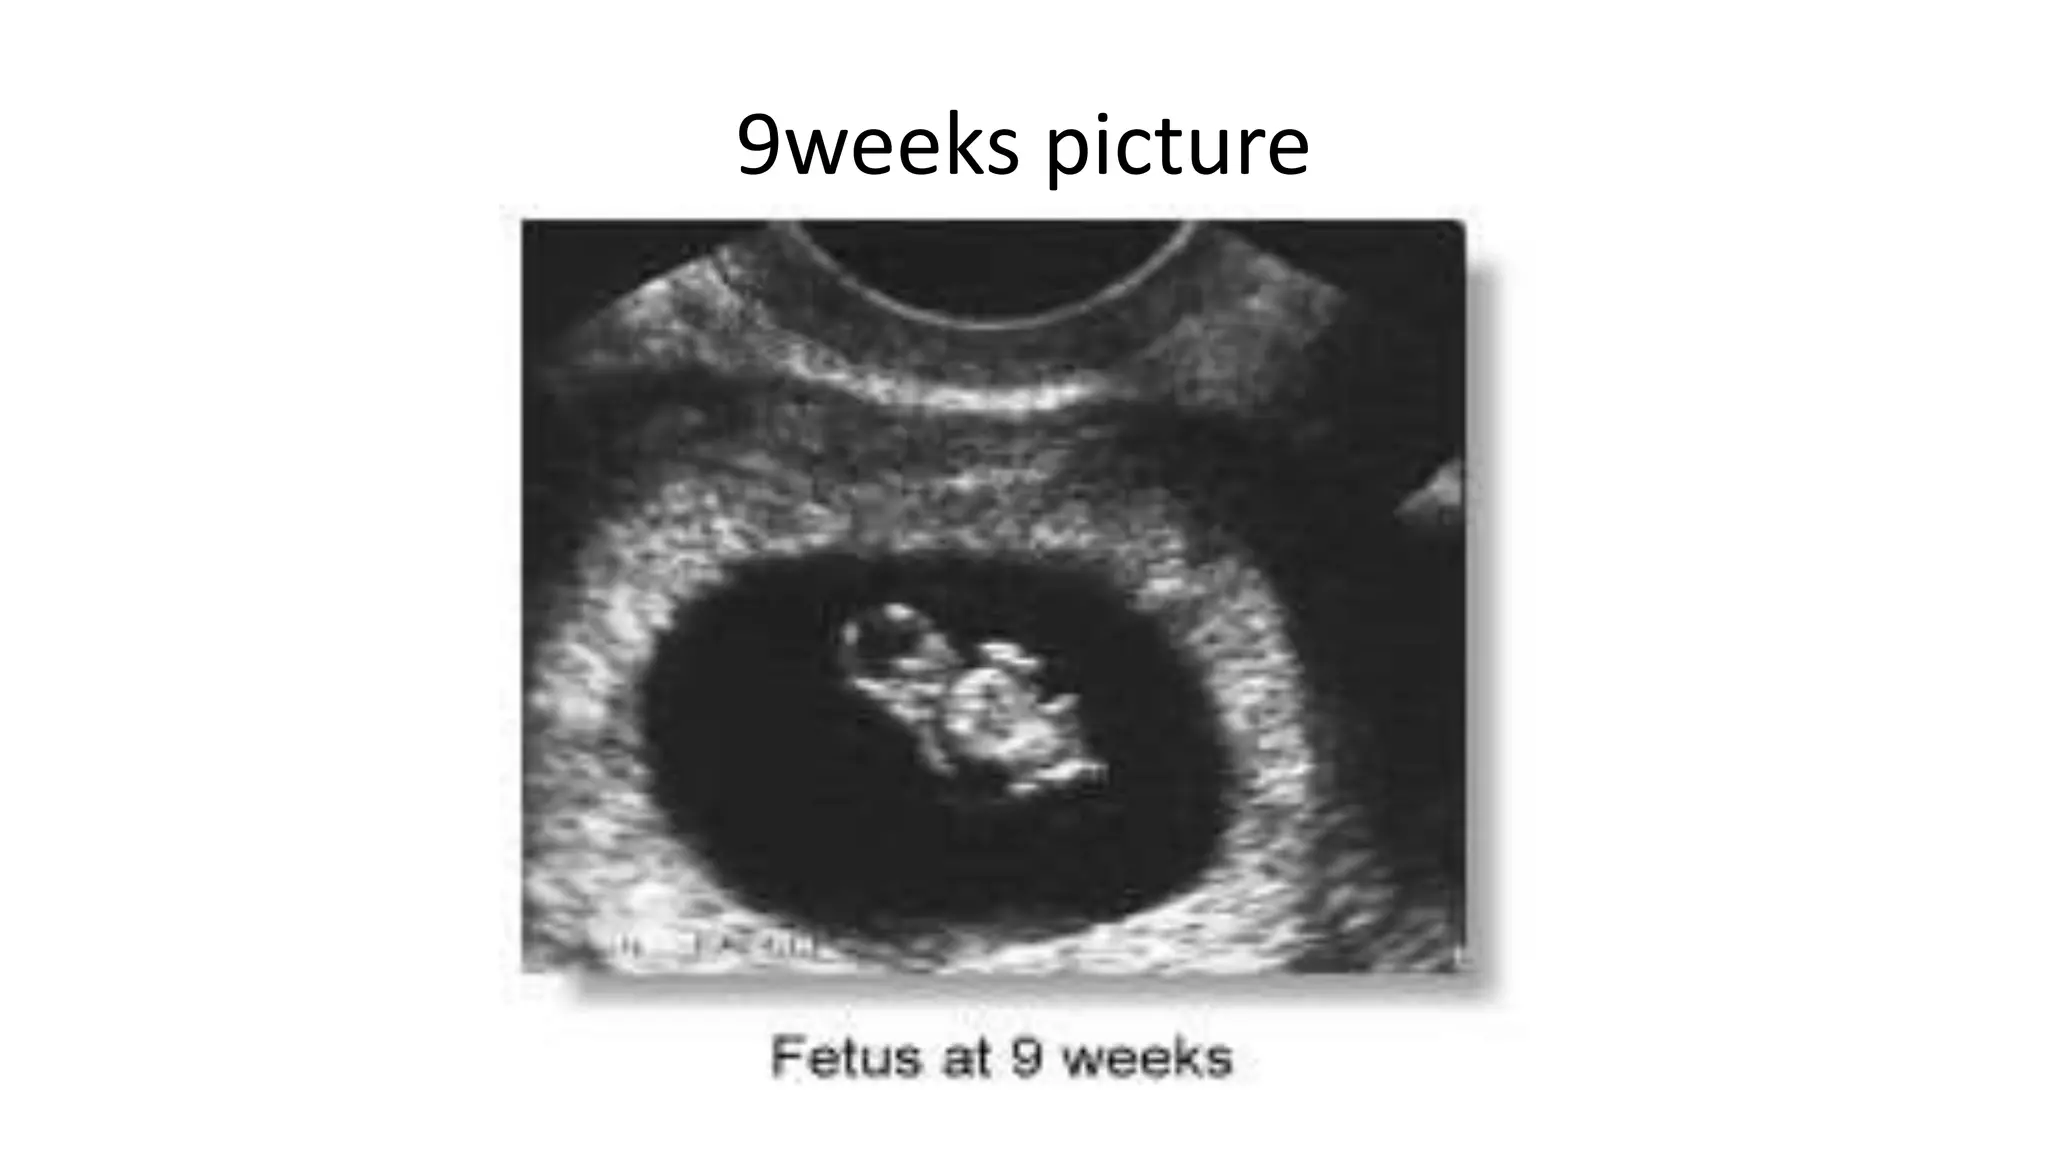

9weeks picture